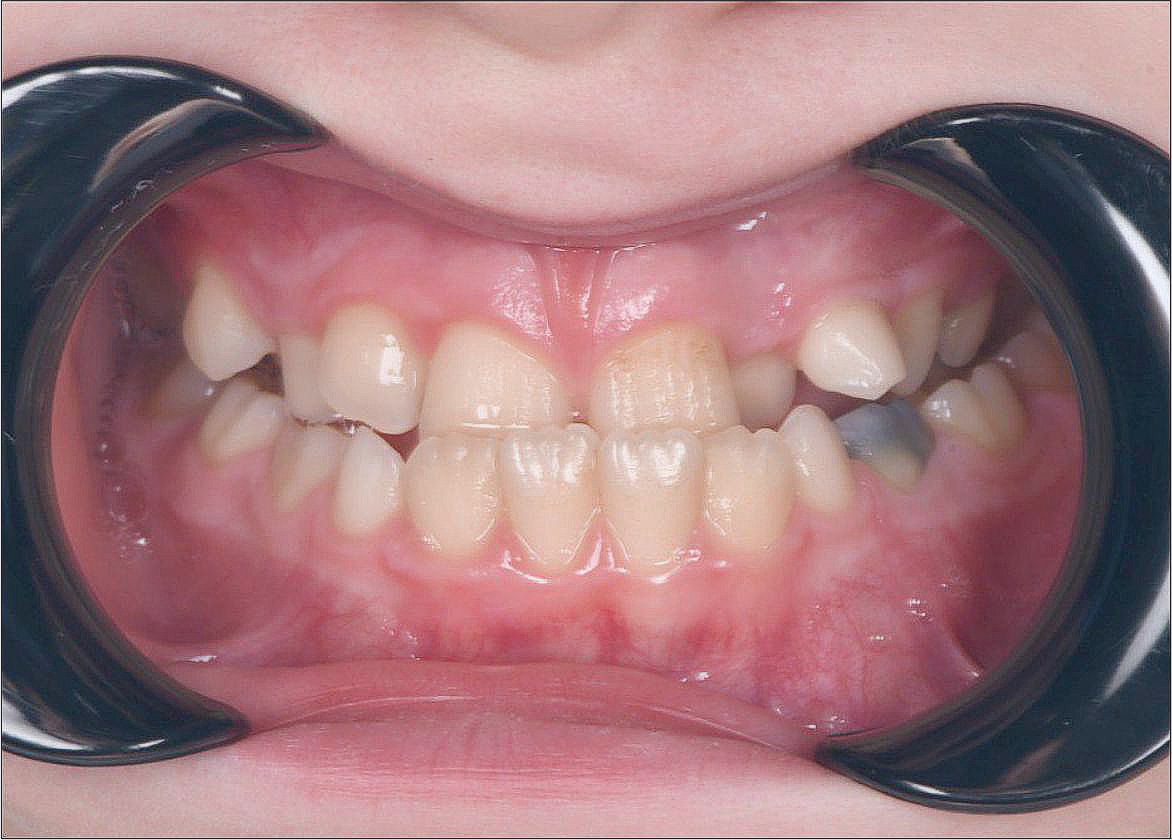

Непростая ситуация, связанная с расположением зубов: лечение кариеса до начала ортодонтического лечения проведено максимально эффективно. Профессионалы своего дела!

Мама мальчика 8 лет обратилась с жалобой: Я вижу, что зуб у сына находится в неправильно положении, возможно ли сейчас это исправить?? Да! Мы достигли результата за 5 месяцев!

В детстве я упал и сломал передний зуб. Тогда мне сделали пломбу. Уже после ортодонтического лечения была проведена реставрация этого зуба. Теперь я очень доволен результатом работы! Спасибо!

У меня всегда было неправильное положение передних зубов. Хочу это исправить!